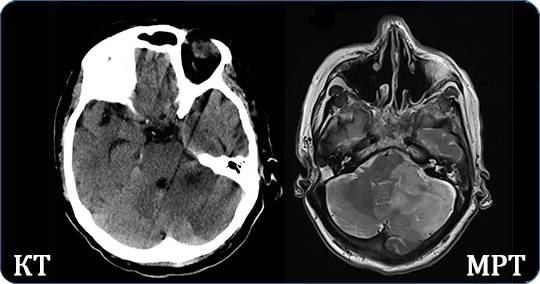

Черепно-мозговая травма на снимках КТ

Сравнение снимков головного мозга методами КТ и МРТ